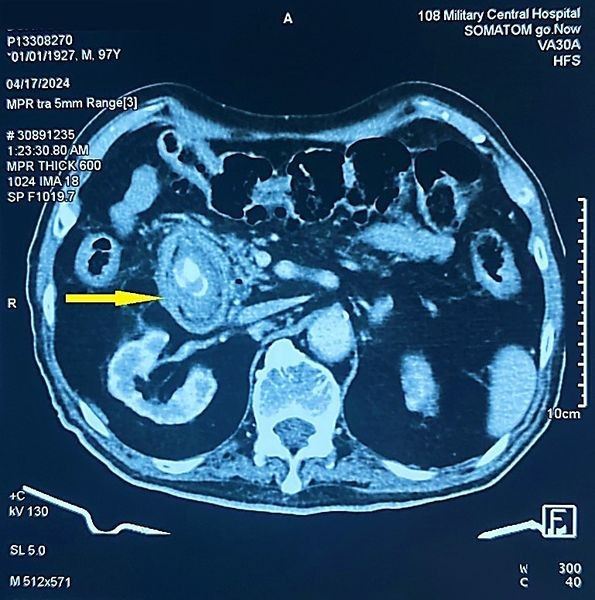

Thông qua hình ảnh chụp cắt lớp vi tính ổ bụng và nội soi tiêu hóa, các bác sĩ chẩn đoán bệnh nhân bị tắc tá tràng do sỏi mật (Hội chứng BOUVERET) kích thước rất lớn 3x5cm rò từ túi mật vào trong lòng tá tràng.

Hình ảnh sỏi trên phim chụp - Ảnh BVCC